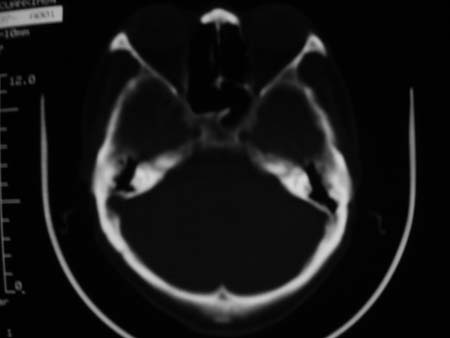

男,54岁,十天前被钢管打伤头顶部,现自述头部不适,视物模糊,并于两天前发觉右枕部有包块,既往未有明显异常.

颅骨多处骨质不完整,内板变薄,右侧额颞部局部呈“穿凿样”骨质缺损,相应区硬膜外密度略增高。多考虑:骨嗜酸性肉芽肿!

右枕骨及双额角均有类似改变,考虑骨髓瘤可能性大,建议查本周氏蛋白.

颅骨多处骨质不完整,内板变薄,右侧额颞部局部呈“穿凿样”骨质缺损,相应区硬膜外密度略增高。多考虑:骨髓瘤或骨嗜酸性肉芽肿!

颅骨多处骨质不完整,内板变薄,右侧额颞部局部呈“穿凿样”骨质缺损,缺损骨质边缘锐利无硬化,相应区硬膜外密度略增高。多考虑:骨嗜酸性肉芽肿!

颅骨多处骨质不完整,内板变薄,右侧额颞部局部呈“穿凿样”骨质缺损,相应区硬膜外密度略增高。多考虑:骨髓瘤或骨嗜酸性肉芽肿!10天前受伤,不会在2天前才发现头部包块,估计与外伤无关.